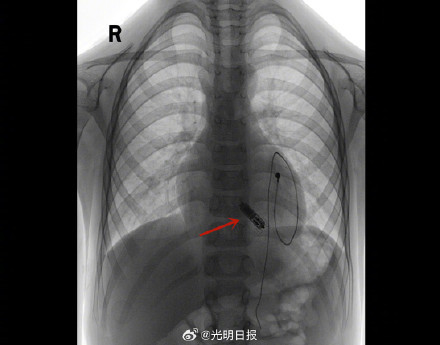

9月4日,6岁的浩浩(化名)从武汉亚洲心脏病医院康复出院,成为国内植入无导线起搏器年龄最小的患者。浩浩因感冒引发暴发性心肌炎,四年前接连实施了两次起搏器植入术,过程波折不断。近日,妈妈带浩浩到武汉亚洲心脏病医院成功实施了第三次起搏器植入术。这次植入的是一枚重量仅2克、大小如“胶囊”,目前世界上最小的无导线起搏器。据介绍,无导线起搏器将在浩浩体内工作长达10-15年,未来可以继续植入新的无导线起搏器,也可更换传统起搏器。(光明日报全媒体记者张锐、王建宏、严德勇)